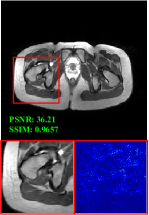

Figure 5 provides the qualitative comparison of the various methods on the four datasets at a scale of 4. The top, second, third, and bottom rows are the SR results under the FastMRI, clinical brain, clinical tumor and clinical pelvic datasets, respectively. The red boxes indicate the zoom-in region of complicated anatomical structures along with their corresponding error maps. Note that the brighter textures in the error maps, the lower the quality of the reconstructed images. As can be seen, compared to methods based on Transformers and CNNs, diffusion-based methods like DisC-Diff and DiffMSR (Ours) are capable of reconstructing high-realistic images with promising reconstruction metric scores (PSNR and SSIM). Nevertheless, while DisC-Diff can reconstruct high-precision MR images, it does not preserve the structure present in the original HR images, introducing some additional information that can affect medical diagnosis. In contrast, our method combines DM and PLWformer, which can preserve the original image’s structure while restoring high-frequency information.

In this section, we present more visual qualitative comparisons. Figures 8, 9, 10, and 11 show the reconstruction results of each method in FastMRI, clinical brain, clinical tumor, and clinical pelvic, respectively. As can be seen, although DisC-Diff can reconstruct MR images with high-frequency information, it fails to preserve the structure and content of the original Target HR image effectively, resulting in image distortion. In contrast, our proposed DiffMSR can restore high-frequency information while preserving the structure of the original HR image, indicating the effectiveness of the joint use of DM and PLWformer.